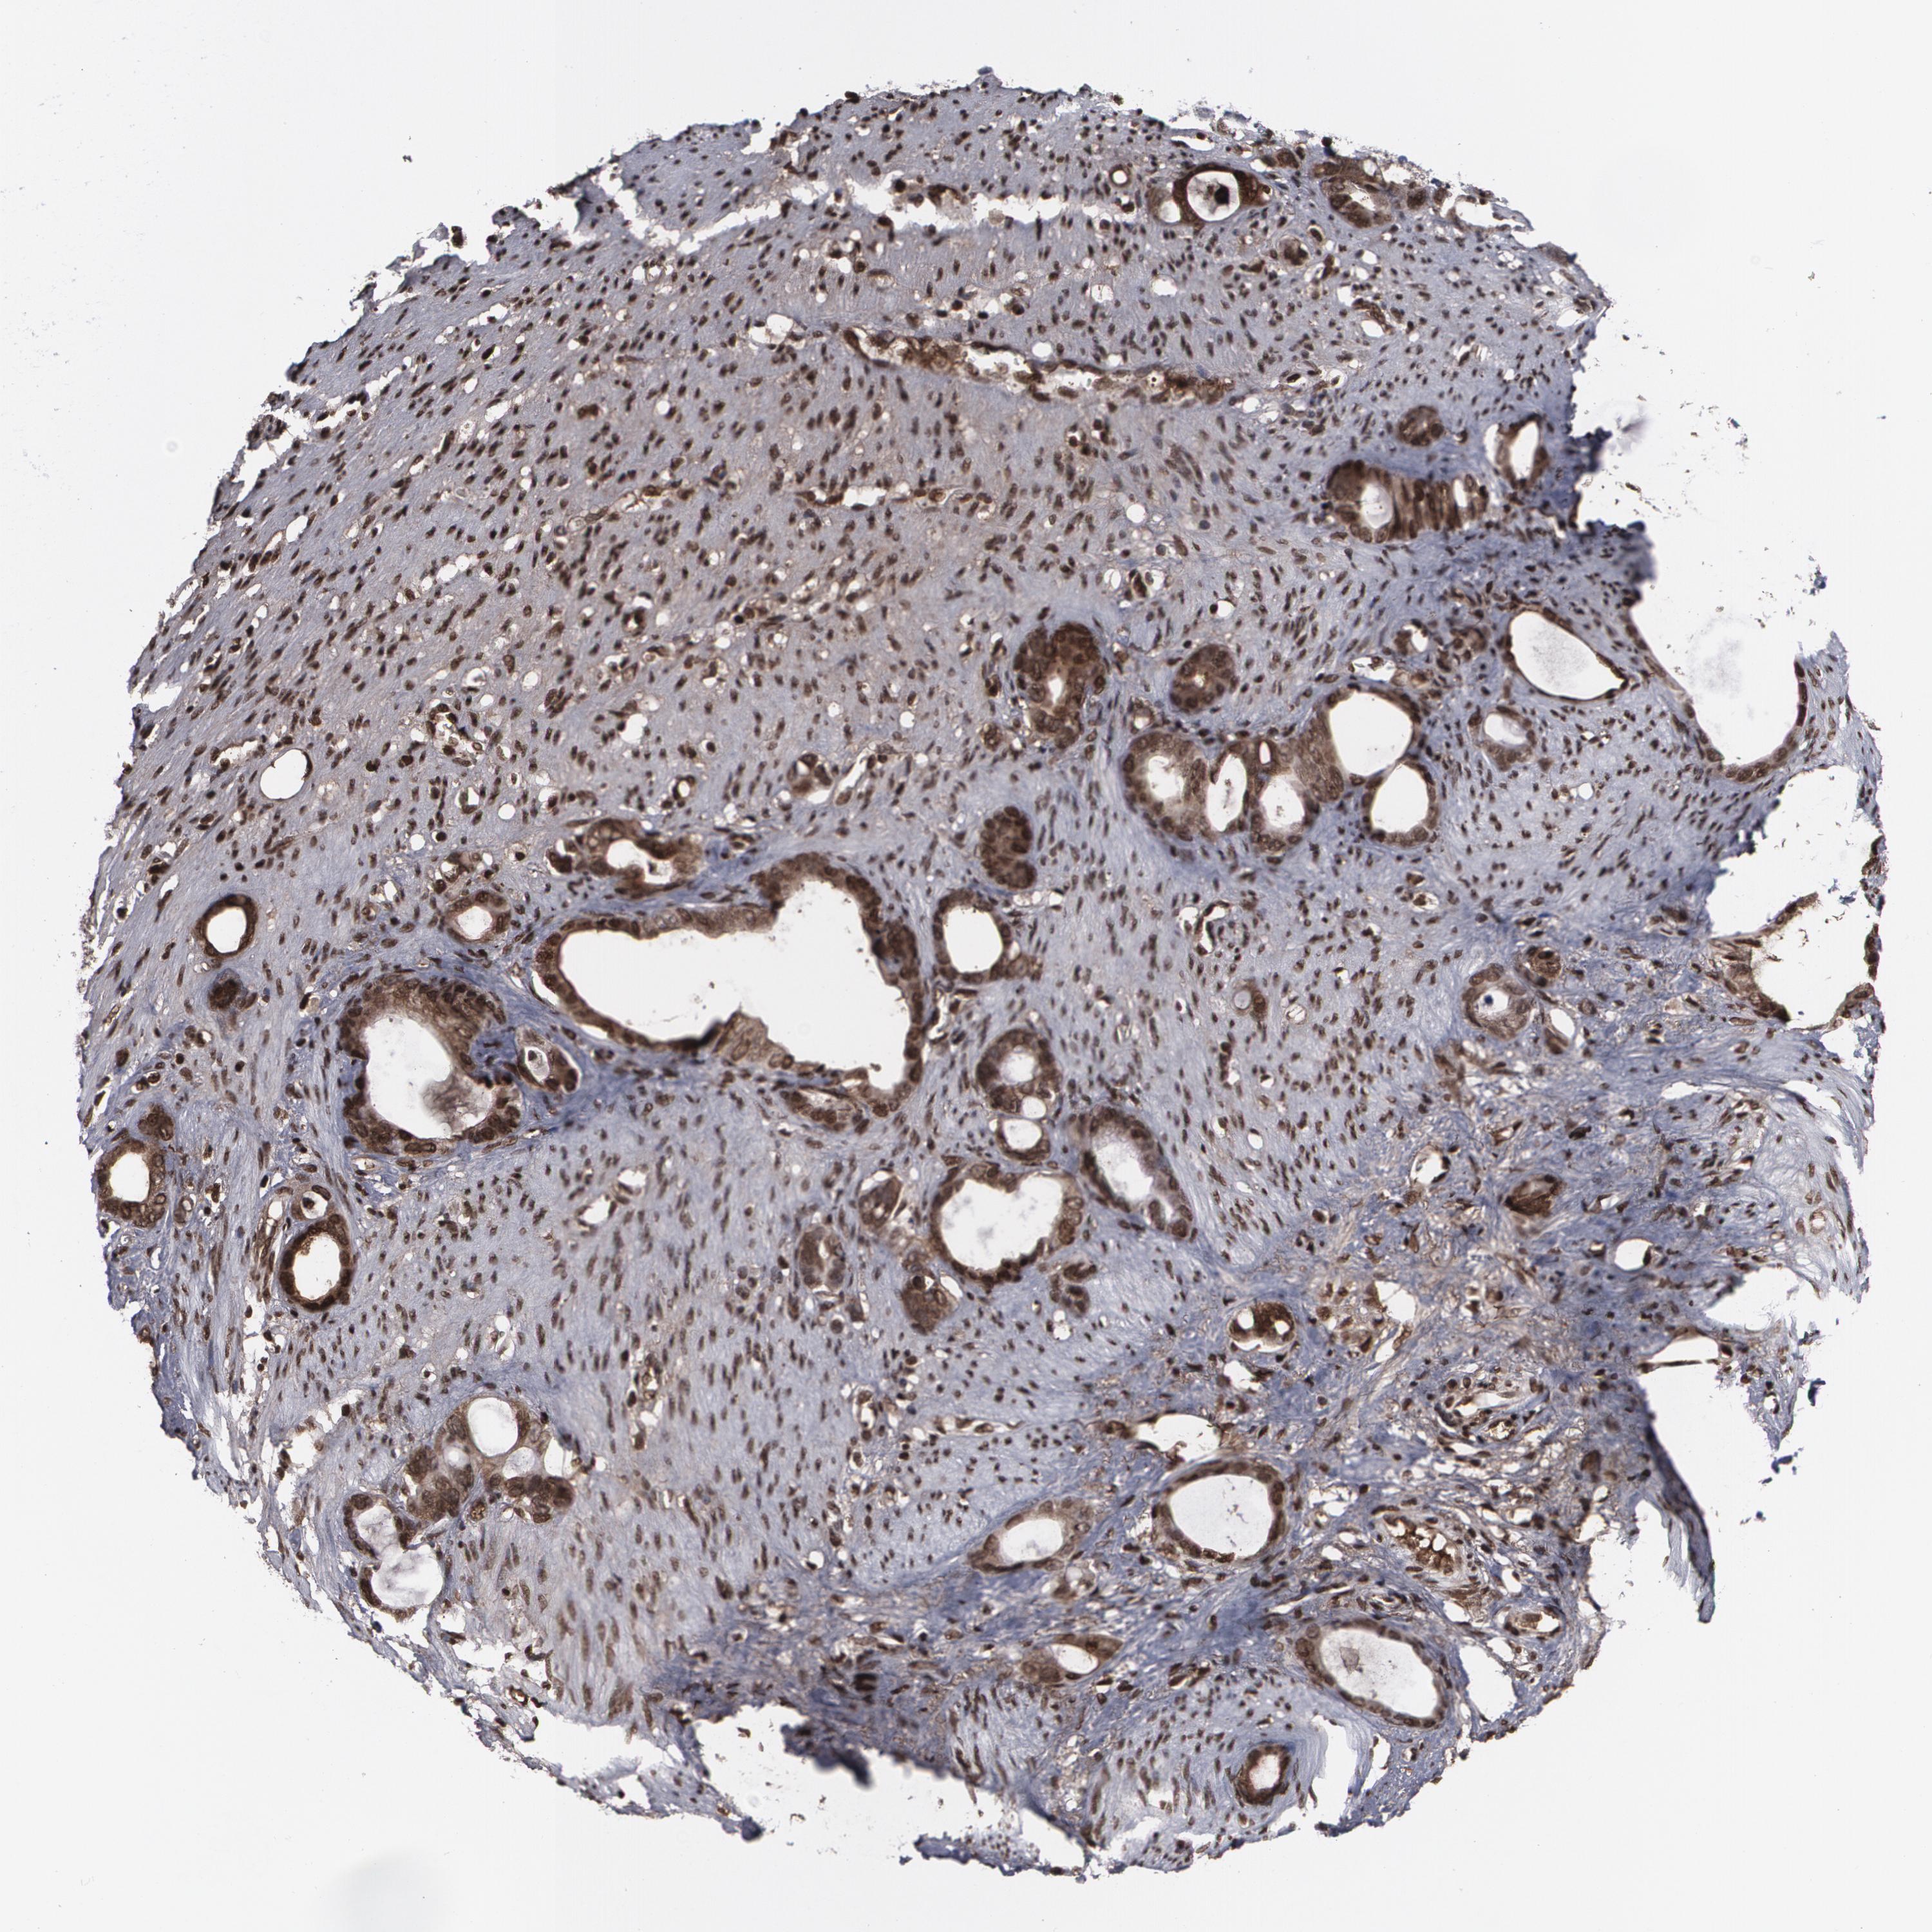

STOMACH CANCER - Protein expressioni

A mouse-over function shows sample information and annotation data. Click on an image to view it in a full screen mode. Samples can be filtered based on level of antibody staining by selecting one or several of the following categories: high, medium, low and not detected. The assay and annotation is described here.

Note that samples used for immunohistochemistry by the Human Protein Atlas do not correspond to samples in the TCGA dataset.

Antibody stainingi

Antibody staining in the annotated cell types in the current human tissue is reported as not detected, low, medium, or high, based on conventional immunohistochemistry profiling in selected tissues. This score is based on the combination of the staining intensity and fraction of stained cells.

Each image is clickable and will lead to virtual microscopy that enables deeper exploration of all samples and also displays staining intensity scores, fraction scores and subcellular localization as well as patient and tissue information for each sample.

Antibody HPA001888

Antibody HPA001889

Staining

High

Medium

Low

Not detected

Intensity

Strong

Moderate

Weak

Negative

Quantity

>75%

75%-25%

<25%

None

Location

Nuclear

Cytoplasmic/membranous

Cytoplasmic/membranous,nuclear

Adenocarcinoma, NOS

Adenocarcinoma, High grade